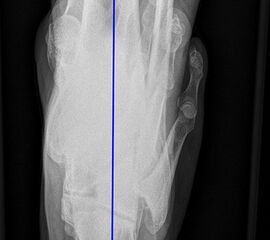

Aufnahmen zur Bestimmung der Bein- und Rückfussachse

Einbeinstandaufnahme

Indikation:

• Beurteilung der Beinachse. Aufnahme zur Planung einer endoprothetischen Versorgung oder zur Planung von Achskorrekturen.

Positionierung:

• Der Patient steht auf beiden Füßen mit gleichmäßiger Lastverteilung.

• Die Kassette befindet sich dorsal des Beins und steht senkrecht zum Boden.

• Die Fußlängsachse verläuft nach ventral.

• Um Verzerrungen zu reduzieren wird die Aufnahme in 3 Teilaufnahmen angefertigt und die Bilder danach digital zusammengefügt.

• Die erste Aufnahme umfasst die Region vom Beckenkamm bis proximales Drittel des Femurs. Der Zentralstrahl ist auf das Hüftgelenk zentriert.

• Die zweite Aufnahme umfasst die distalen zwei Drittel des Femurs und das proximale Viertel der Tibia. Der Zentralstrahl ist auf das Kniegelenk zentriert.

• Die dritte Aufnahme umfasst die distalen Dreiviertel der Tibia mit Fuß und Sprunggelenk. Der Zentralstrahl ist wird mittig auf das Sprunggelenk zentriert.

• Die Röntgenröhre steht bei allen drei Aufnahmen 0° horizontal

Kennzeichen des Röntgenbildes:

• Abbildung des gesamten Beins.

• Die Aufnahme ist Basis aller Achskorrekturen.

• Zur Bestimmung der Beinachse wird die Mikulicz-Linie eingezeichnet. Sie verläuft vom Hüftkopfmittelpunkt zur Mitte der Talusrolle.

• Bei einer physiologischen Beinachse verläuft diese Linie durch die Mitte des Kniegelenkes (Eminentia intercondylaris des Tibiaplateaus). Beim Genu varum (O-Bein) verläuft die Mikulicz-Linie medial der Eminentia interconylaris, beim Genu valgum (X-Bein) lateral der der Eminentia interconylaris.

Besondere Bemerkungen zum Beispielbild:

• Valgusarthrose des Sprunggelenks.

• Diskret varische Beinachse bei medial betonter Arthrose des Kniegelenks.

• Lateral des OSG ist eine Eichkugel eingeblendet, die als Referenz bei der Planung von Endoprothesen dient.

• Verkalkung medial in den Weichteilen des Unterschenkels.